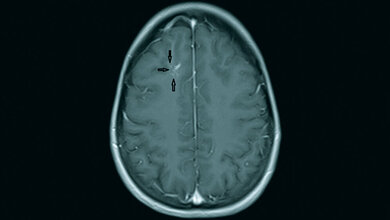

Anomalien und Normvarianten – Interne Veränderungen 2.18: Maldescensus testis

Der Maldescensus testis ist die häufigste genitale Malformation der Jungen und hat ein erhöhtes Risiko der Infertilität und malignen Entartung. Die Therapie mit humanem Choriongonadotropin ist oft erfolgreich, sonst die operative Behandlung mit Orchiopexie.